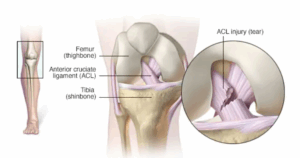

Knee pain

Knee pain is a common complaint that affects people of all ages. Knee pain may be the result of an injury, such as a ruptured ligament or torn cartilage. Medical conditions — including arthritis, gout and infections — also can cause knee pain.